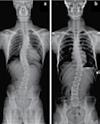

교통사고 후유증 / 목 통증 / 목 디스크 / 오십견 / 어깨통증

말초신경장애: 손, 발, 다리의 통증, 저림, 근육약화감, 감각상실 (편)두통 / 불면증 / 어지러움 / 턱관절 장애(TMJ)

척추측만증(Scoliosis) / 척추협착증 / 허리수술 후유증

허리통증 / 허리 디스크 / 관절염 / 좌골신경통 / 고관절, 발목, 손목 통증